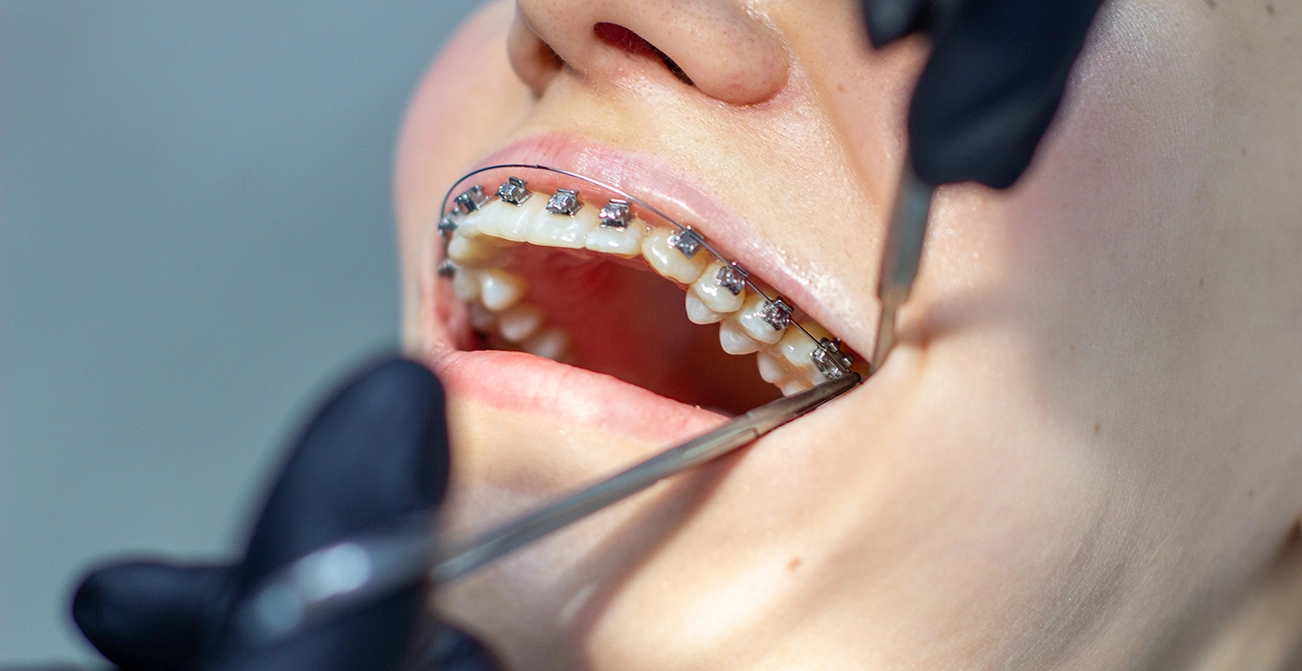

利用金屬或陶瓷矯正器搭配弓絲,精確控制牙齒移動。由於適應症範圍廣,特別適合牙齒移動量較大或複雜咬合問題的患者。

金屬矯正器堅固耐用,陶瓷矯正器則外觀較不顯眼,但無論哪種,都需注意固定式矯正器可能造成食物殘渣堆積,因此日常清潔需更細心。

利用金屬或陶瓷矯正器搭配弓絲,精確控制牙齒移動。由於適應症範圍廣,特別適合牙齒移動量較大或複雜咬合問題的患者。金屬矯正器堅固耐用,陶瓷矯正器則外觀較不顯眼,但無論哪種,都需注意固定式矯正器可能造成食物殘渣堆積,因此日常清潔需更細心。

傳統金屬 / 陶瓷固定式矯正